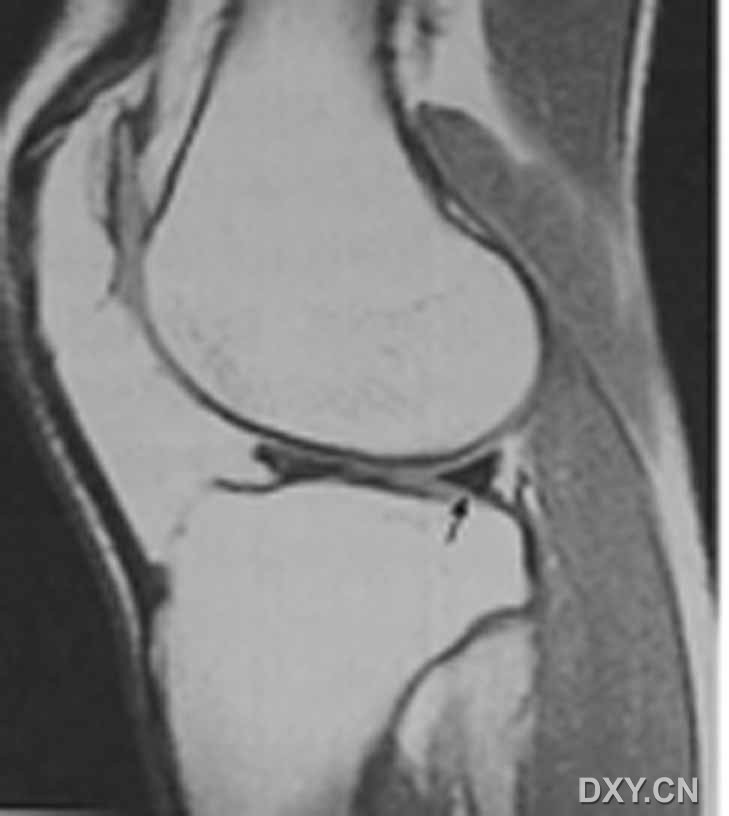

| 半月板斜行撕裂 斜行高信号影达半月板的下关节面缘 A:矢状T1 B:矢状T2

| 半月板斜行撕裂 斜行高信号影达半月板的下关节面缘 C:矢状STIR D:冠状T1